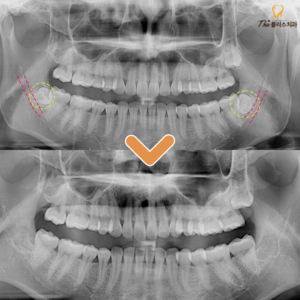

17. 수암동치과 신경관과 가까운 경우에도

수암동치과 신경관과 가까운 경우에도   안녕하세요. 모든 진료에 진심을 다하는 곳, 더플러스치과입니다. ​ 사랑니를 생각하면 공포감을 먼저 느끼는 분들이 많으실 텐데요.   주변의 경험담이나 본인이 겪은 발치 경험으로 좋지 않은 이미지를 떠올리게 됩니다.   사랑니는 영구치 중에서도 마지막에 맹출하며,   더보기…